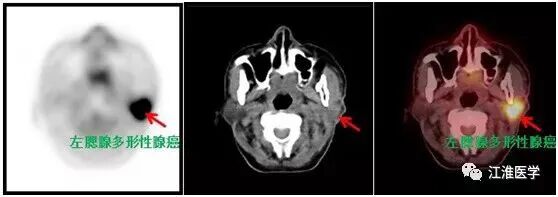

老张的结果,可想而知,下面的图诉说着血淋淋的故事:

图中左侧的黑白图除了大脑,心脏和膀胱外其余的黑点全是肿瘤病灶,右边的十字指示的是腮腺的复发的恶性肿瘤